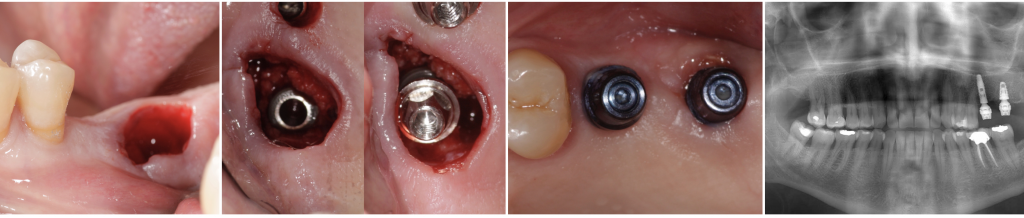

Fig.3- Immediate implant (Alvim, Neodent®) with the definitive Micro-abutment placed the same day of the surgery.

The CM connection has a virtual absence of microgap and, therefore, of micro-movements (Weng 2011). It allows bone overgrowth beyond the implant platform (Degidi 2008, Weng 2011).

Linkevicius et al., suggested that dimensional bone changes occurred during biologic width formation, considering the soft-tissue thickness as a key parameter and not just the platform switching (Linkevicius 2010). Degidi et al. introduced the definitive abutment at the same time of the implantation (Degidi 2013). We screwed to the implant the definitive abutment to help to preserve the initial biologic the same day of the implant surgery with favorable results.